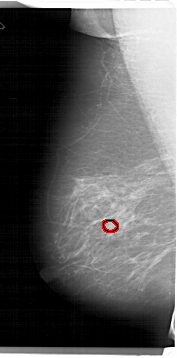

A_1335_1.LEFT_MLO

FILE: A_1335_1.LEFT_MLO.OVERLAY

TOTAL_ABNORMALITIES 1

ABNORMALITY 1

LESION_TYPE MASS SHAPE OVAL MARGINS OBSCURED

ASSESSMENT 3

SUBTLETY 3

PATHOLOGY BENIGN

TOTAL_OUTLINES 1

BOUNDARY